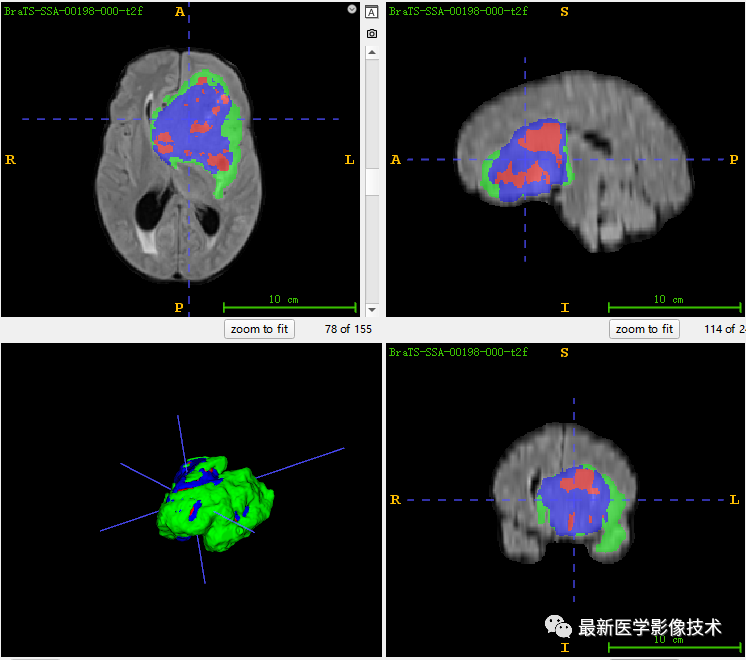

6、验证集分割结果

左图是金标准结果,右图是网络预测结果。